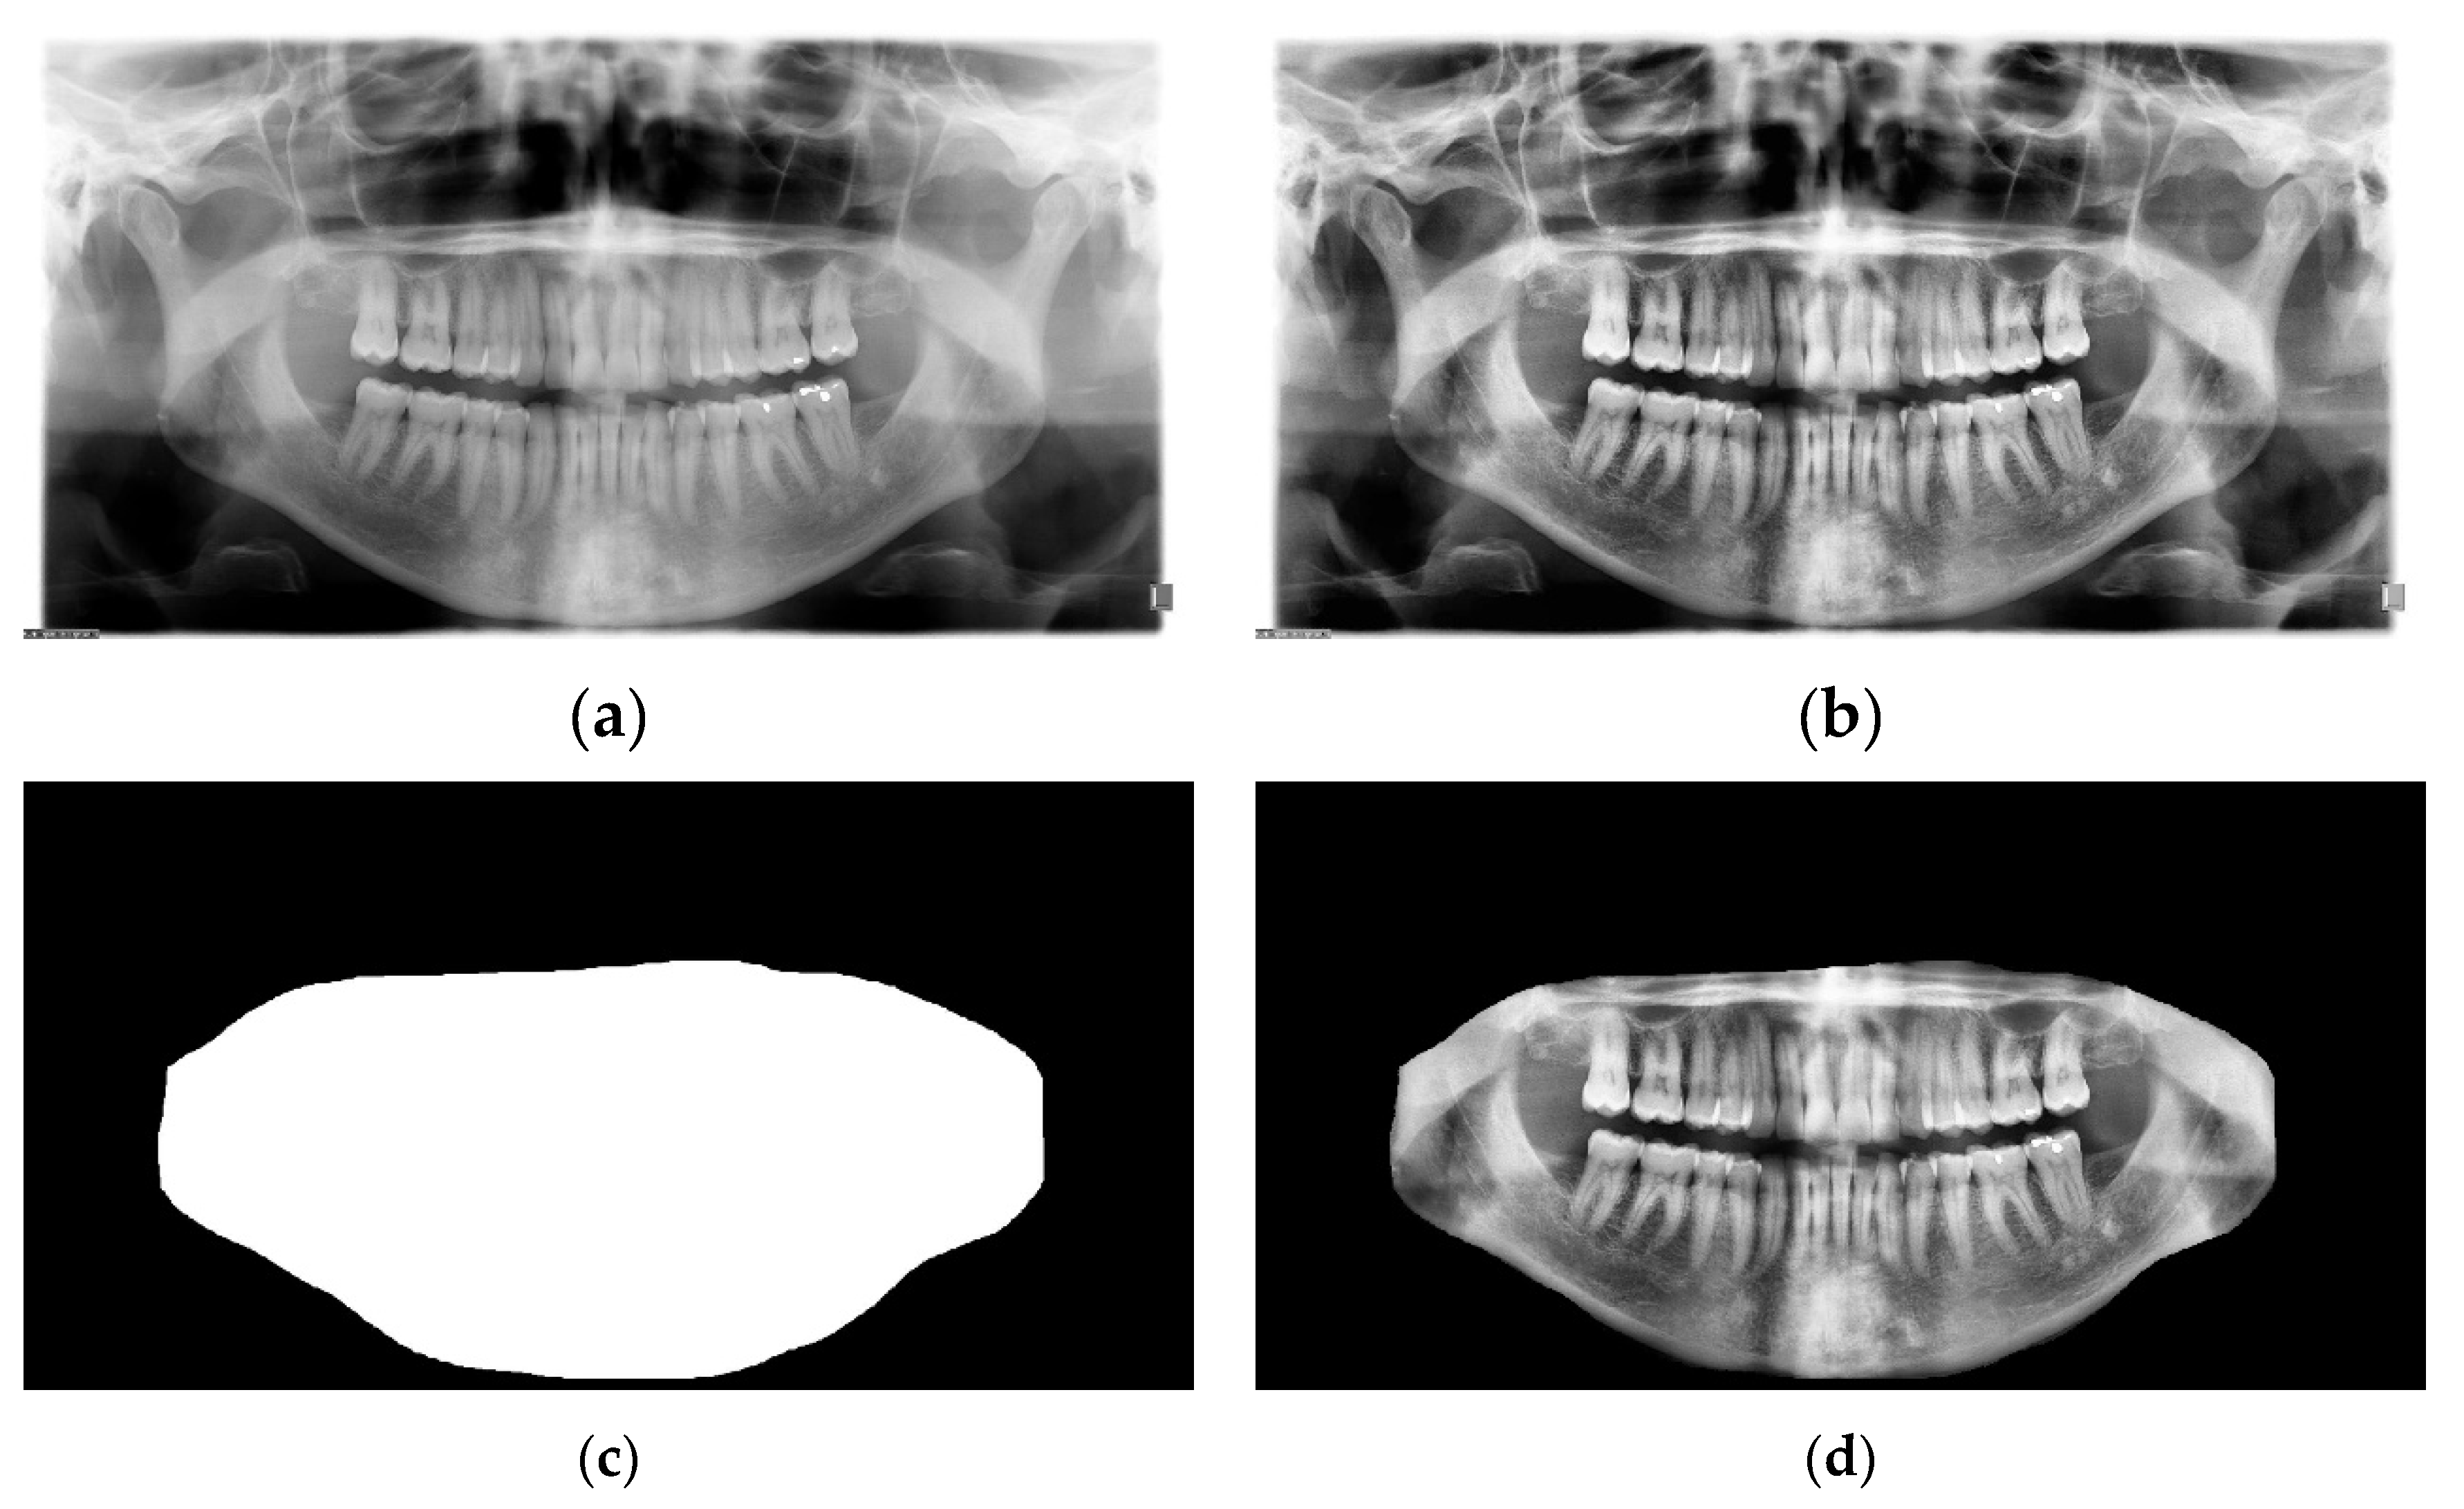

The TUFTS university dataset [41] is a multimodal dataset consisting of 1000 de-identified images of panoramic radiographs shown in Figure 9b and five other major components such as 1) teeth masks in Figure 9d. ,2) maxillomandibular masks shown in Figure 9c, 3) eye tracker generated maps (grey and quantized), 4) text information containing the description of each radiograph, and 5) masks outlining the abnormalities. Each abnormality segmentation mask and the radiograph description are further split into expert and student-level annotations. The classification of the radiographs is based on five categories: peripheral characteristics, anatomical location, radiodensity, effects on the surrounding structure, and the abnormality category, making it a multimodal dataset. The folder structure of the dataset is shown in Figure 9a.

The preprocessing process is as follows: Contrast Limited Adaptive Histogram Equalization (CLAHE) [43] was applied to the images to enhance the image features. The contrast enhancement process had a major impact on the visibility of the images. Figure 11b and Figure 11a show the original and enhanced image, respectively. To further yield better performance from the model, the maxillomandibular mask shown in Figure 11c was used by applying an AND operation to the maxillomandibular mask with the preprocessed image to get only the ROI that includes the teeth shown in Figure 11d. Finally, the processed radiograph shown in Figure (11d) and its corresponding ground truth mask shown in Figure 9d was resized to 512 × 256. The preprocessing was applied to all examples in the dataset. Figure 10 is a diagram showing the preprocessing pipeline.

Figure 9. (a) Description of the folder structure of the TUFTS dataset. The "Radiographs" folder contains images like the one shown in (b), the folder "maxillomandibular" includes images like the one shown in (c), and the folder named "teeth_mask" contains images like the one shown in (d).

Figure 11. The preprocessing steps for the dataset. (a) is the original image, (b) after applying the Contrast Limited Adaptive Histogram Equalization. (c) is the maxillomandibular mask highlighting the ROI, and (d) is the final image after doing an AND operation on (b) with (c).